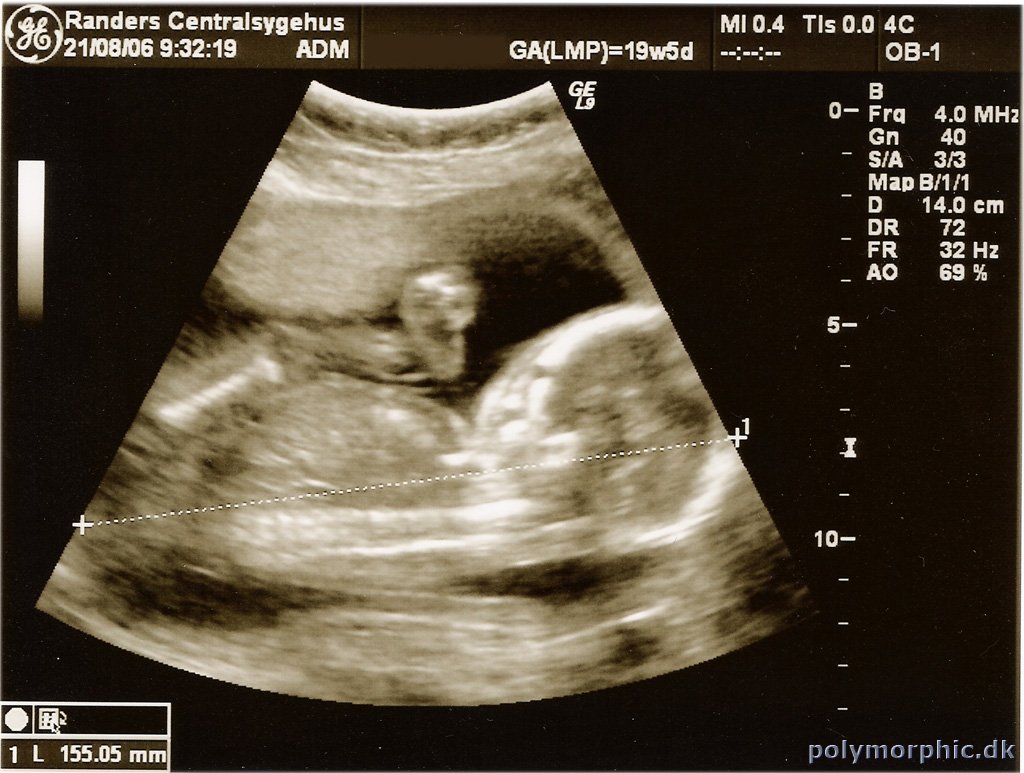

Anden scanning

Så har vi være til anden scanning, også kaldet misdannelses scanning. Men det var der heldigvis ikke noget af, så alt er helt som det skal være.

Barnet måler nu 15,5 cm fra hoved til hale og hovedet er 5,5 cm i diameter.

Selvom der ikke er noget som er 100% sikkert, tyder alt på at det bliver en pige. :)

Billeder fra scanningen kan ses her: